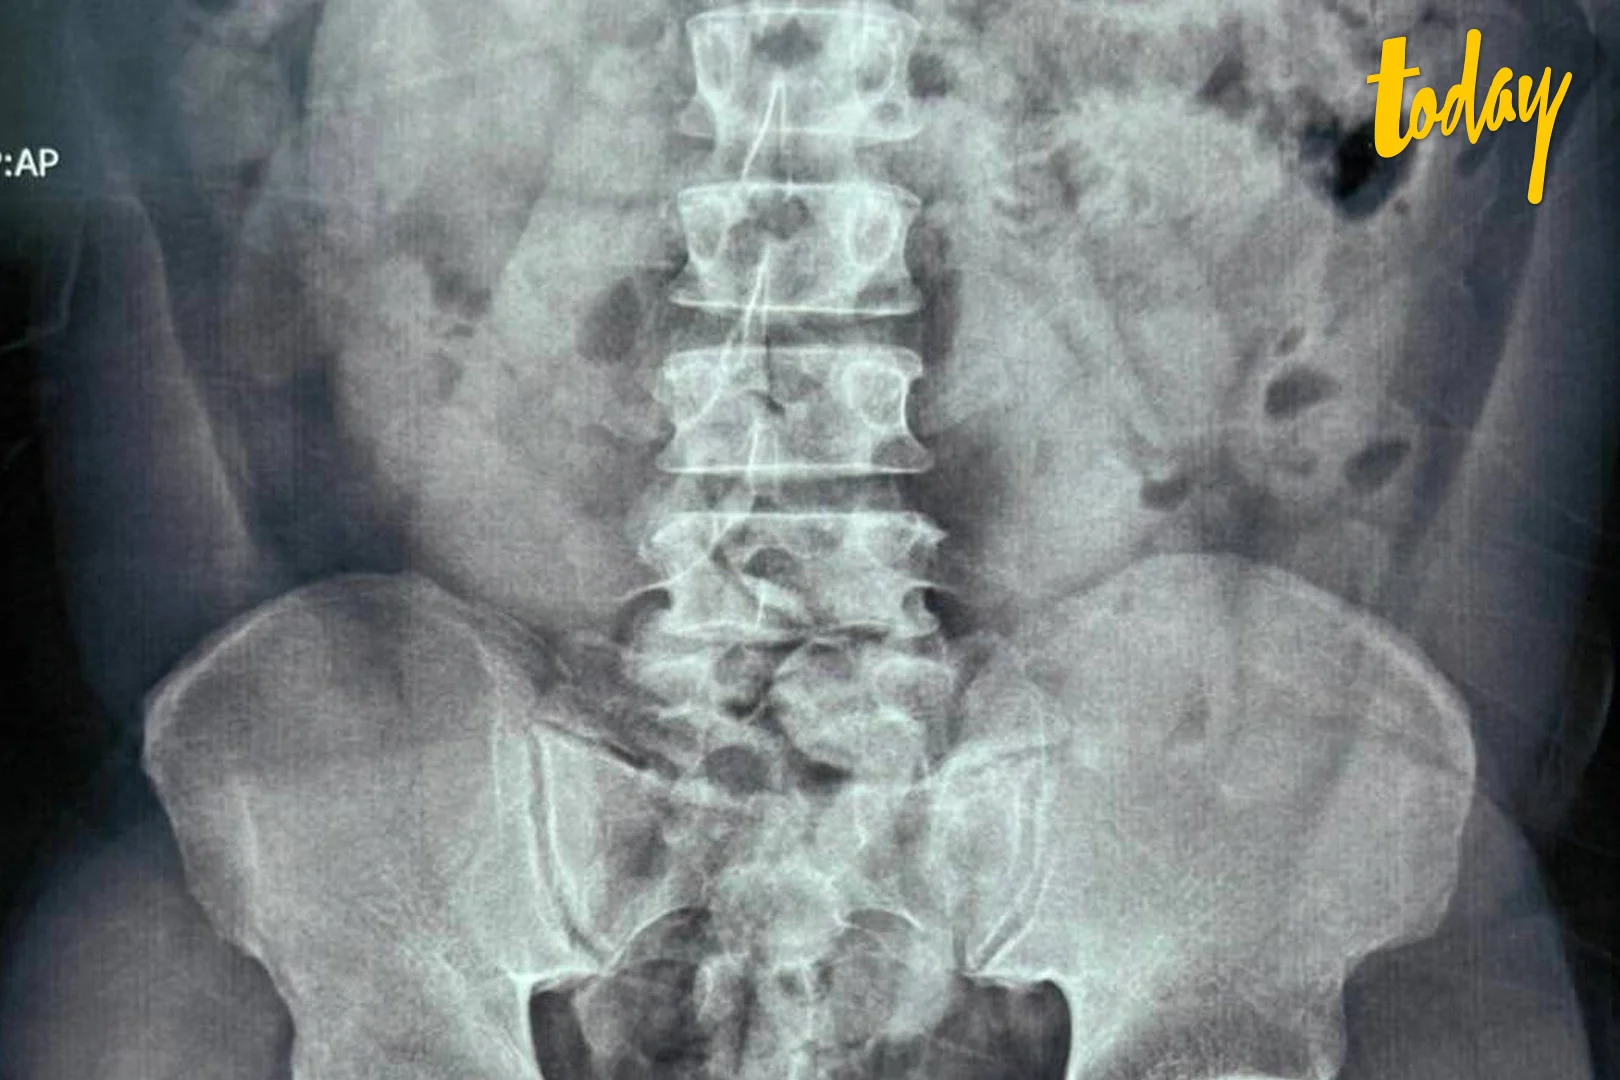

เจ้าหน้าที่กรมศุลกากรและเจ้าหน้าที่ชุดปฏิบัติการ AITF จึงจัดชุดสังเกตการณ์ด้านนอกโรงแรม จนในวันที่ 6 มี.ค. 2565 เวลา 10.00 น. ผู้โดยสารคนดังกล่าวได้ออกจากโรงแรมกักตัว เจ้าหน้าที่ได้เข้าตรวจค้นและนำตัวไปทำการเอกซเรย์ที่โรงพยาบาล ผลเอกซเรย์บ่งชี้ว่า ผู้ต้องหามีสิ่งแปลกปลอมในช่องท้อง จึงได้นำตัวผู้ต้องหาไปทำการขับถ่ายที่สำนักงานสุวรรณภูมิ เสร็จสิ้นเมื่อวันที่ 8 มี.ค. 2565

นายชัยยุทธ กล่าวว่า จากการตรวจสอบพบวัตถุแปลกปลอมเป็นยาเสพติดประเภทโคเคน จำนวน 54 ก้อน น้ำหนักรวม 1,080 กรัม มูลค่าประมาณ 3,240,000 บาท จึงได้แจ้งข้อหาให้ชายคนดังกล่าวทราบว่า การกระทำดังกล่าวเป็นความผิดฐานนำเข้ายาเสพติดให้โทษประเภท 2 และครอบครองยาเสพติดให้โทษประเภท 2 โดยไม่ได้รับอนุญาต ตามประมวลกฎหมายยาเสพติด และเป็นความผิดตามมาตรา 244 แห่งพระราชบัญญัติศุลกากร พ.ศ. 2560 จากนั้นนำผู้ต้องหาพร้อมของกลางส่งพนักงานสอบสวนดำเนินคดี